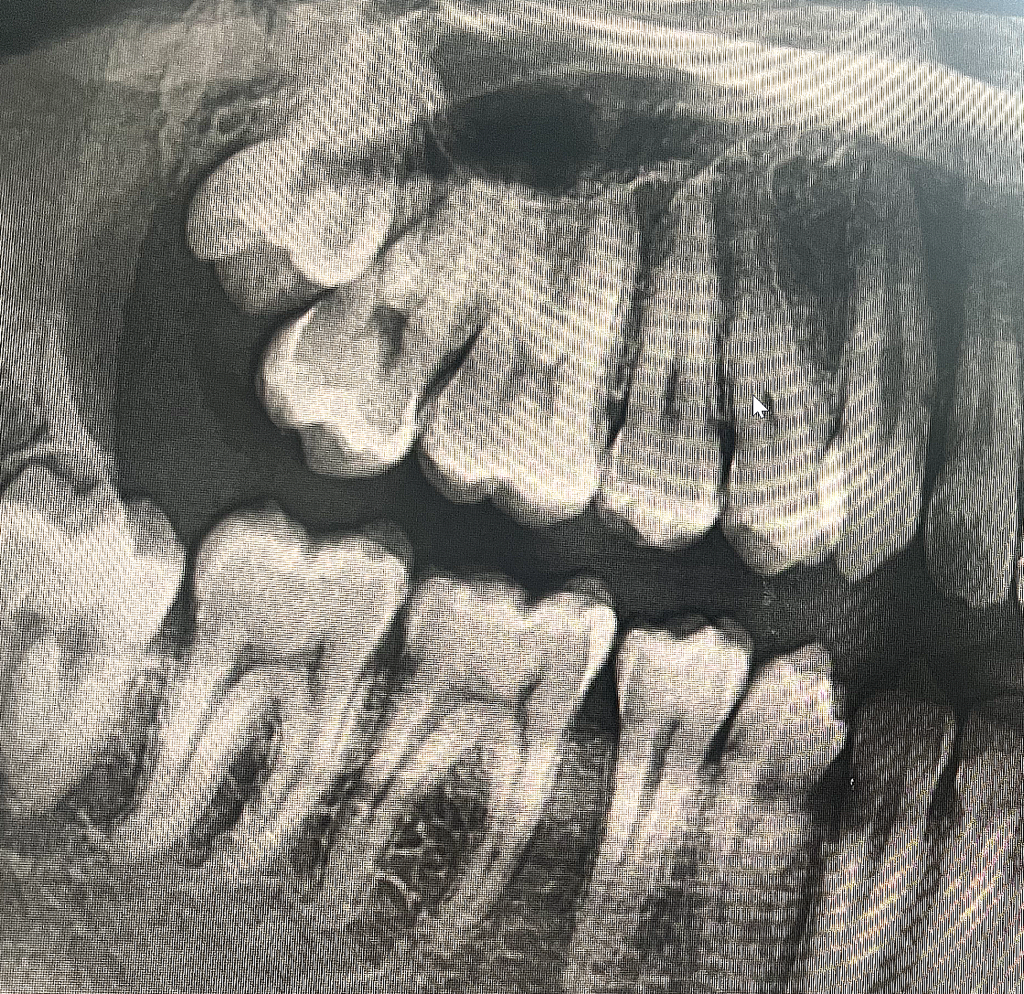

엑스레이 및 구강사진으로 충치진단

어떤 치아를 어떤 치료해야할지 알려주세요

• 2번 째 사진

치아 사이에 즉, 인접면 충치가 다수 있으신거 같습니다. 저정도면 진행되는 충치이니 치료를 하시는게 좋을것같습니다.